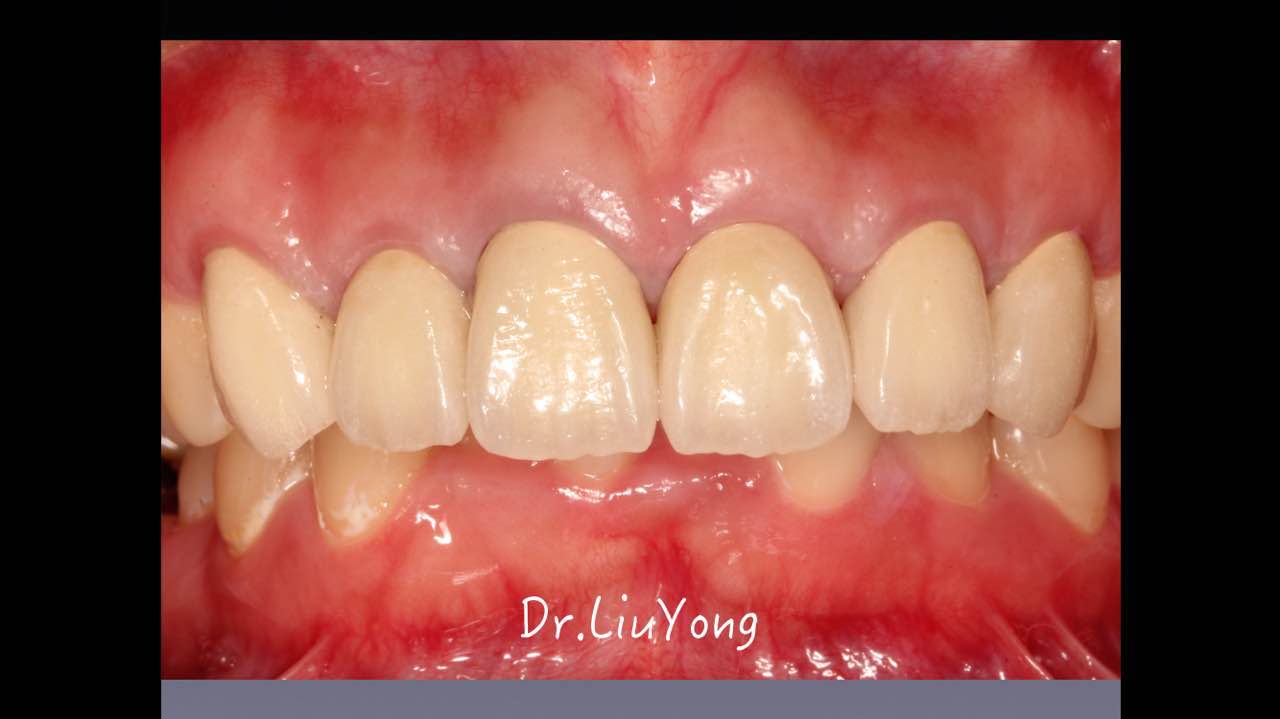

嚴重破壞生物學寬度,根尖瘺管,重行根管治療, 第一次冠延長建立唇腭側(cè)及鄰面BW,術后牙齦扇貝形差, 齦乳頭黑三角,再次行美學冠延長,建立牙齦扇貝形,手術免費, 患者因經(jīng)濟原因只能選擇鑄樁及鈷鉻合金烤瓷冠。終于完工